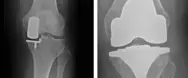

Delprotese i knæ giver gode resultater

Delprotese i knæet giver et bedre resultat med god bevægelighed og mindre risiko for komplikationer sammenlignet med en total knæprotese.

Delprotese vs helprotese

Delprotese (uniknæ) kan anbefales til patienter, der kun har slidgigt i det ene ledkammer - hyppigst på indersiden af knæet. Dette er tilfældet for ca. 30 - 50% af alle patienter med slidgigt i knæet.

Indsættelse af en delprotese i knæet er et mindre indgreb, hvor risikoen for komplikationer såsom infektion og blodpropper er mindre sammenlignet med en total knæprotese.

Sandsynligheden for at opnå et rigtigt godt resultat efter operationen er bedre sammenlignet med totale knæproteser. Bevægeligheden bliver ofte bedre, og chancerne for at kunne ligge på knæ efter operationen er større.